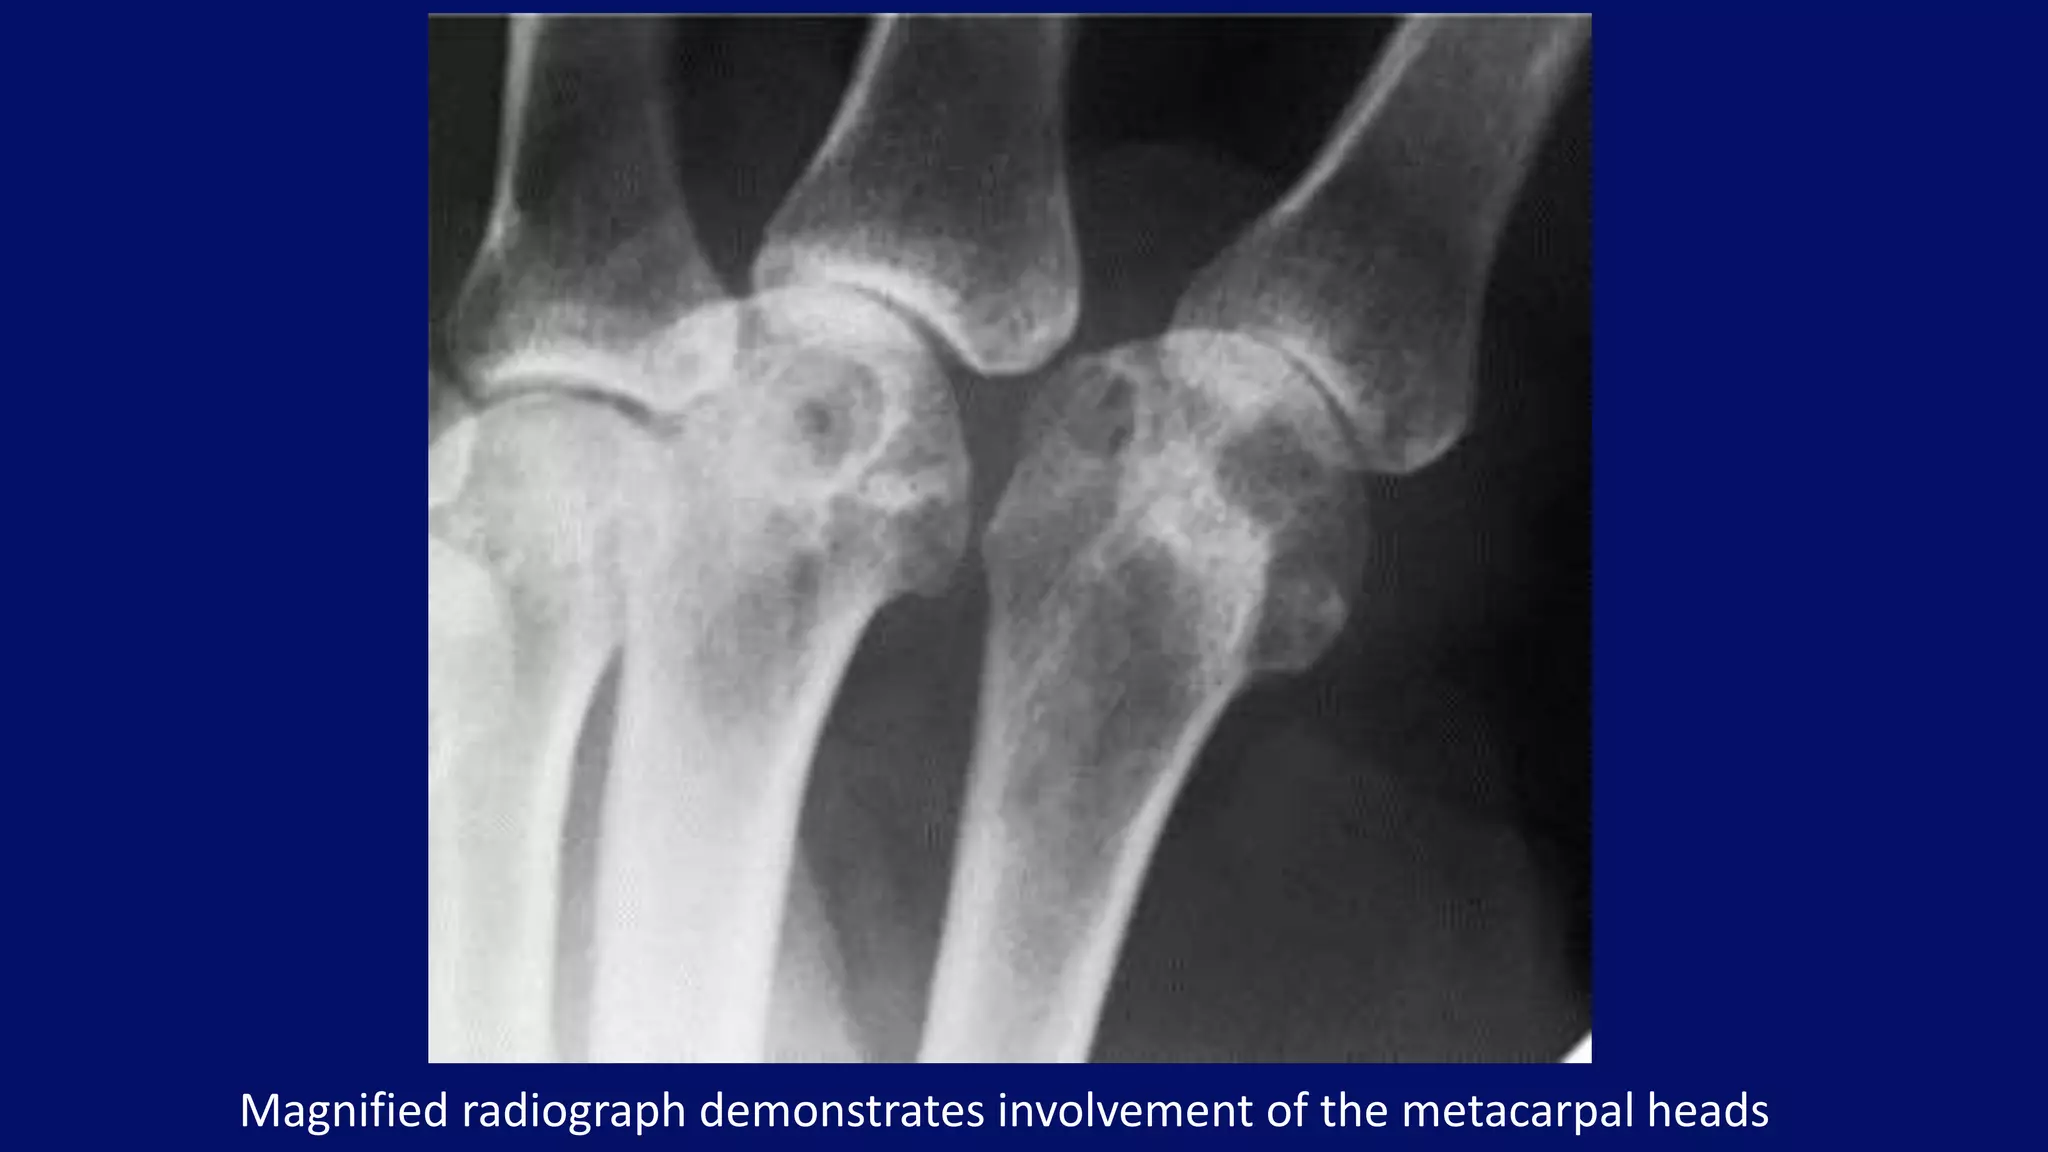

Magnified radiograph demonstrates involvement of the metacarpal heads

• #112 A coned-down magnified radiograph of the second and third metacarpophalangeal joints of the right hand demonstrates characteristic involvement of the metacarpal heads.

• #110 thers is relative sparing of IP joint with invovlment of MCP joints Another typical feature of the disease is the presence of hook-like osteophytes generally seen on the radial aspect of the metacarpal heads. Chondrocalcinosis is seen in association with the metacarpal changes, usually best appreciated in the wrist.

• #114 Oblique radiographs of both hands of a 53-year-old woman with hemochromatosis show beak-like osteophytes arising from the heads of the second and third metacarpals on the radial aspect. The interphalangeal, metacarpophalangeal, and carpal articulations are also affected